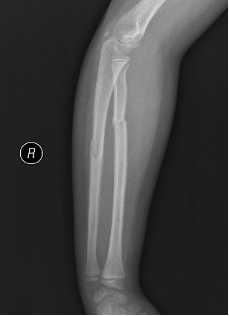

手術前X片:提示患兒尺橈骨干雙骨折,尺橈骨斷端有成角、短縮及移位

手術后X片:提示患兒尺橈骨骨折解剖復位,彈性髓內(nèi)釘置入準確到位